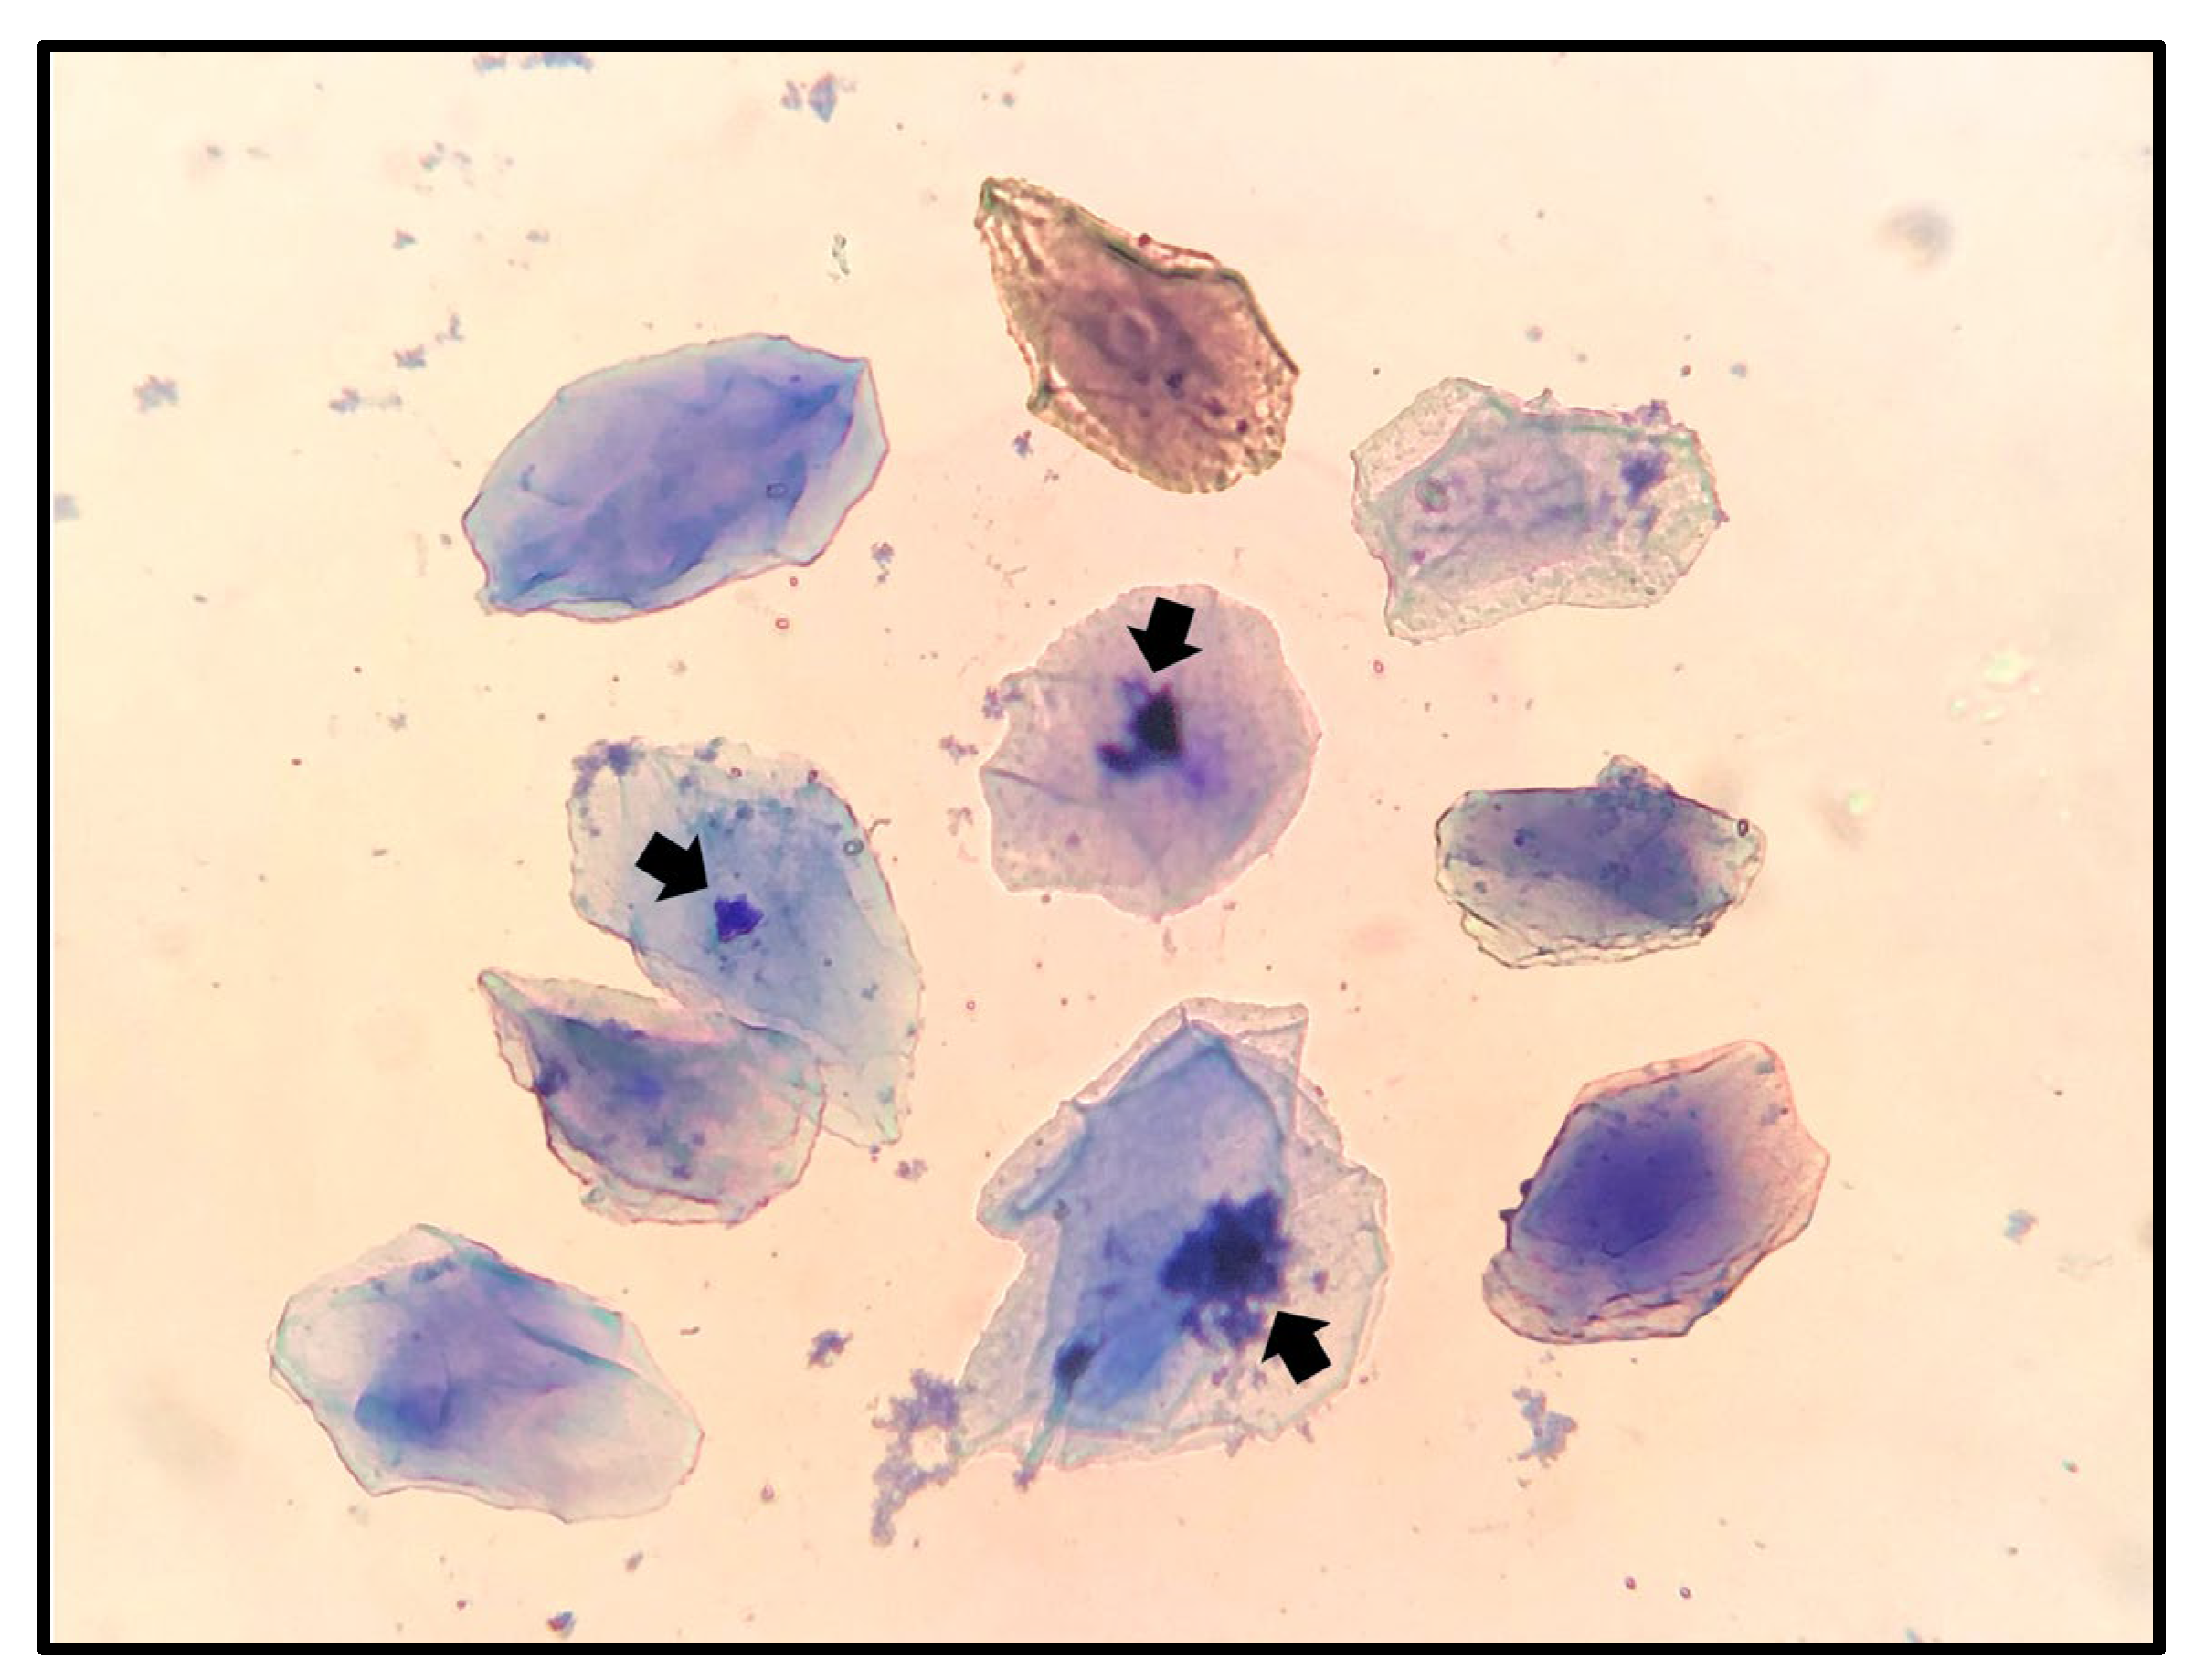

The present study evaluated the efficacy of human chorionic gonadotropin (hCG)-induced ovulation in Maine Coon queens under subtropical conditions, with catteries managed outdoors or indoors under controlled photoperiods. Seven queens in proestrus or estrus were selected based on vaginal cytology and received a single intramuscular injection of 100 IU hCG to induce ovulation. Serum progesterone levels were measured 24 hours post-treatment, and fertile toms were introduced for mating. All queens ovulated, became pregnant, and delivered within a 4-day window, with a mean gestation length of 67.9 ± 2.1 days. The mean litter size was 6.2 ± 3.2 kittens, significantly larger than historical records for the cattery (p ≤ 0.05), while neonatal mortality at birth was low (4.5%). These outcomes indicate that the applied protocol reliably induces ovulation, enhances fertility, and improves perinatal survival. The study also highlights breed-specific reproductive traits of Maine Coons, including late sexual maturity, large litter size, and susceptibility to spontaneous ovulation. Exogenous hCG administration was well tolerated, with no adverse effects observed. Overall, the findings support the use of hCG-induced ovulation as a practical and effective strategy for reproductive management in Maine Coon breeding programs, particularly under controlled environmental conditions, enabling optimization of litter timing, size, and neonatal survival.

- Kanca, H.; Karakas, K.; Dalgic, M.A.; Salar, S.; Izgur, H. Vaginal Cytology after Induction of Ovulation in the Queen: Comparison of Postoestrus and Dioestrus. Aust Vet J 2014, 92, 65–70. [Google Scholar] [CrossRef]